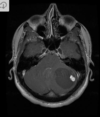

A

Cisto epidermóide

Hipersinal na difusão

Sinal heterogêneo no FLAIR

Extra-axial

Cisto epidermóide do SNC

Sinal heterogêneo no FLAIR e Hipersinal na DWI

Extra-axial nas sisternas da base.